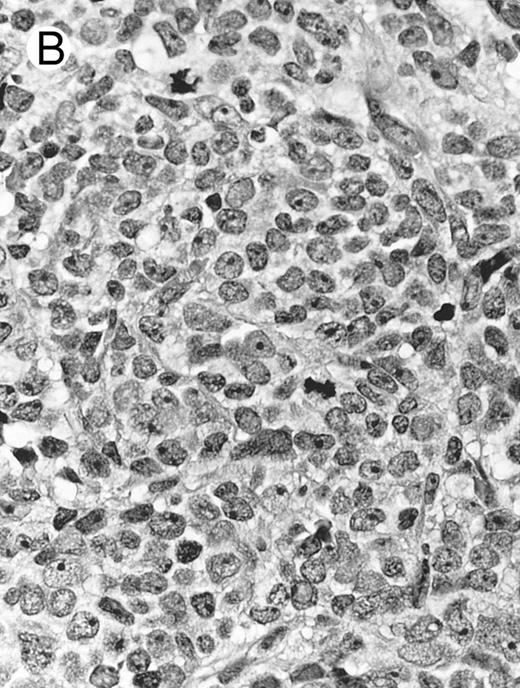

Histologically, the lymphomatous infiltrate was diffuse or patchy, with angiocentric and angiodestructive growth being observed in 30 cases (88.2%) (Figs 1 and 2). The cytologic composition was variable from case to case, including predominance of small cells, medium-sized cells, or large cells, or a mixture of these cell types (Fig 2 and 3). The tumor cell nuclei frequently showed irregular foldings and granular chromatin (Fig 2B). The larger cells possessed distinct nucleoli. The cytoplasm was moderate in amount and often pale. Karyorrhexis was usually prominent. Zonal tumor cell death, focal or confluent, was evident in 27 cases. In the 14 cases for which Giemsa-stained touch preparations were available, azurophilic granules could be identified in at least some of the neoplastic cells.

Lymph node biopsy of aggressive NK cell leukemia/lymphoma (case no. 37). There is a fairly monotonous, diffuse infiltrate of medium-sized cells with round nuclei. The neoplastic cells in this case resemble plasmacytoid monocytes.